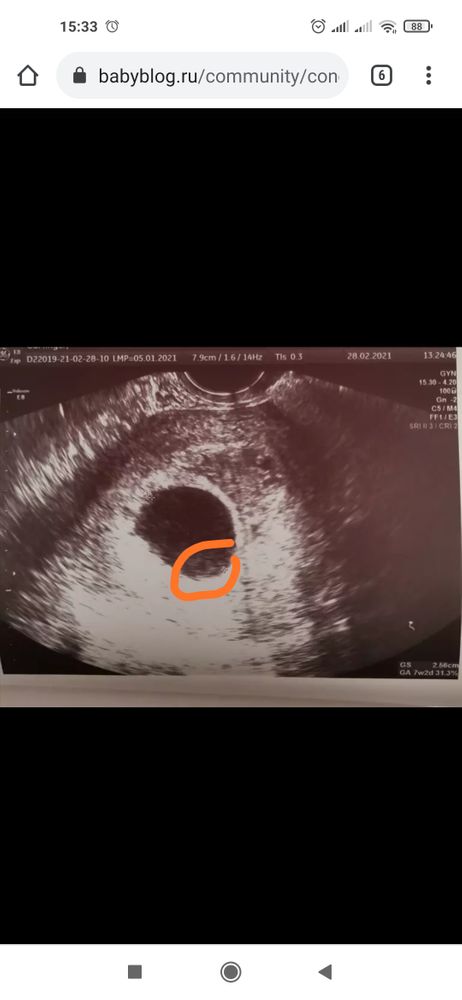

Людмила

Мария //рожу дочку в 2021//,

Это разве не жм?Может сходить к другому специалисту. В любом случае подождите ещё чуть-чуть

Мария //рожу дочку в 2021//

Везде пишут что при таком размере ПЯ уже ничего не появится(( тем более даже ЖМ нет. На фото видимо так вышло, как ни крутили не было его. Конечно перед процедурой ещё раз УЗИ сделаю, но надежд почти нет